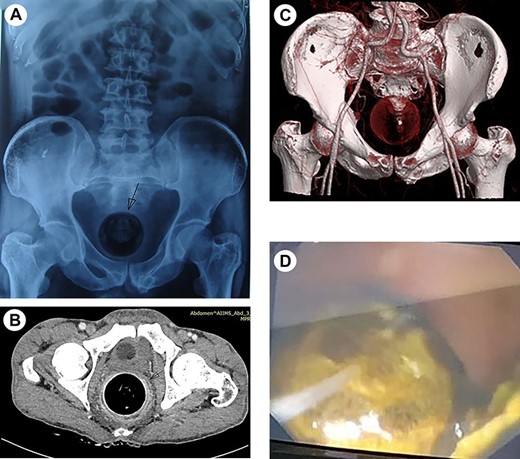

The patient was further evaluated with flexible rectoscopy confirming the impacted mass, as endoscope failed to pass beyond it. Transabdominal ultrasonography, abdominal radiography and computed tomography (CT) scan of abdomen were obtained. CT scan demonstrated a large well-defined rounded peripherally hyperdense, internal hypodense object, likely a foreign body of size 5.7 × 5.6 cm noted in rectum causing focal distension of rectum with grossly dilated proximal bowel (Fig. 1a–d). Laboratory values were unremarkable. A differential diagnosis of foreign body or faecaloma in rectum leading to bowel obstruction was made.

(a) Abdominal X-ray showing round foreign body in the rectum with dilated bowel loops. (b) CECT (axial) abdomen showing impacted foreign body in rectum and (c) the reconstruction image of foreign body in rectum. (d) Rectoscopic image showing rectal mass.